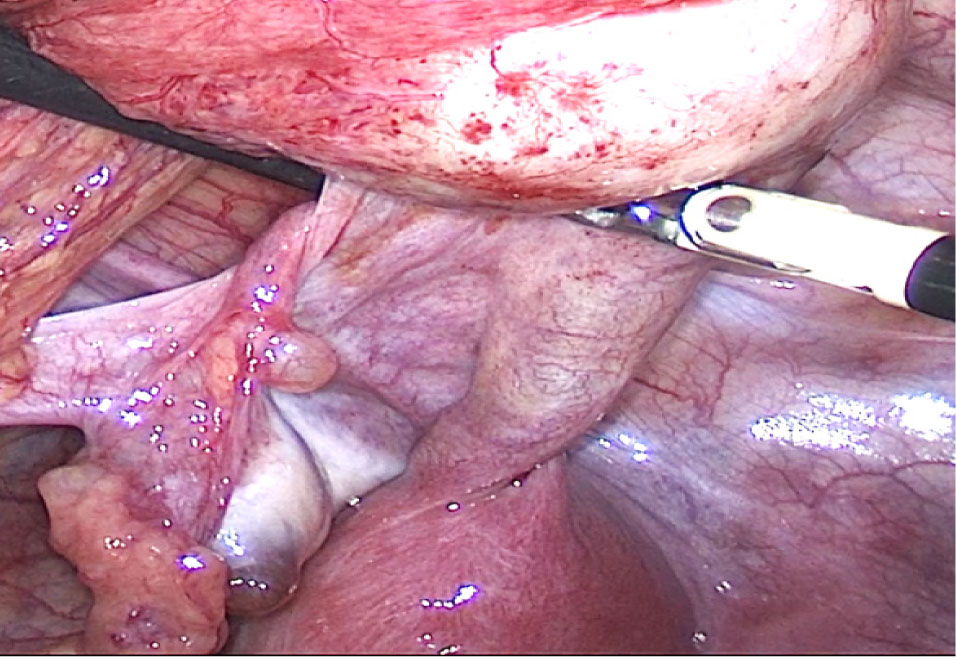

24.09.2024 г. выполнена диагностическая лапароскопия, интраоперационно обнаружено: тело матки представлено состоятельным правым маточным рогом размерами около 5 × 4,5 см, имеющим шейку матки, к которой на уровне внутреннего зева подходят крестцово-маточные связки, и интимно прилегающим к нему замкнутым левым маточным рогом округлой формы около 4 см в диаметре, слепо заканчивающимся на уровне внутреннего зева. От левого рога матки отходит отечная маточная труба, расширеннная в истмическом отделе до 3 см и в ампулярном отделе до 6 см, слепо заканчивающаяся – напряженный гематосальпинкс. К левому яичнику прилежит рудиментарный фимбриальный отдел левой маточной трубы, связанный с гематосальпинксом соединительнотканным «тяжем» (рис. 3, 4).

Рис. 3. Диагностическая лапароскопия. Аномалия развития матки

Рис. 4. Диагностическая лапароскопия. Рудиментарный фимбриальный отдел левой маточной трубы, соединенный с гематосальпинксом